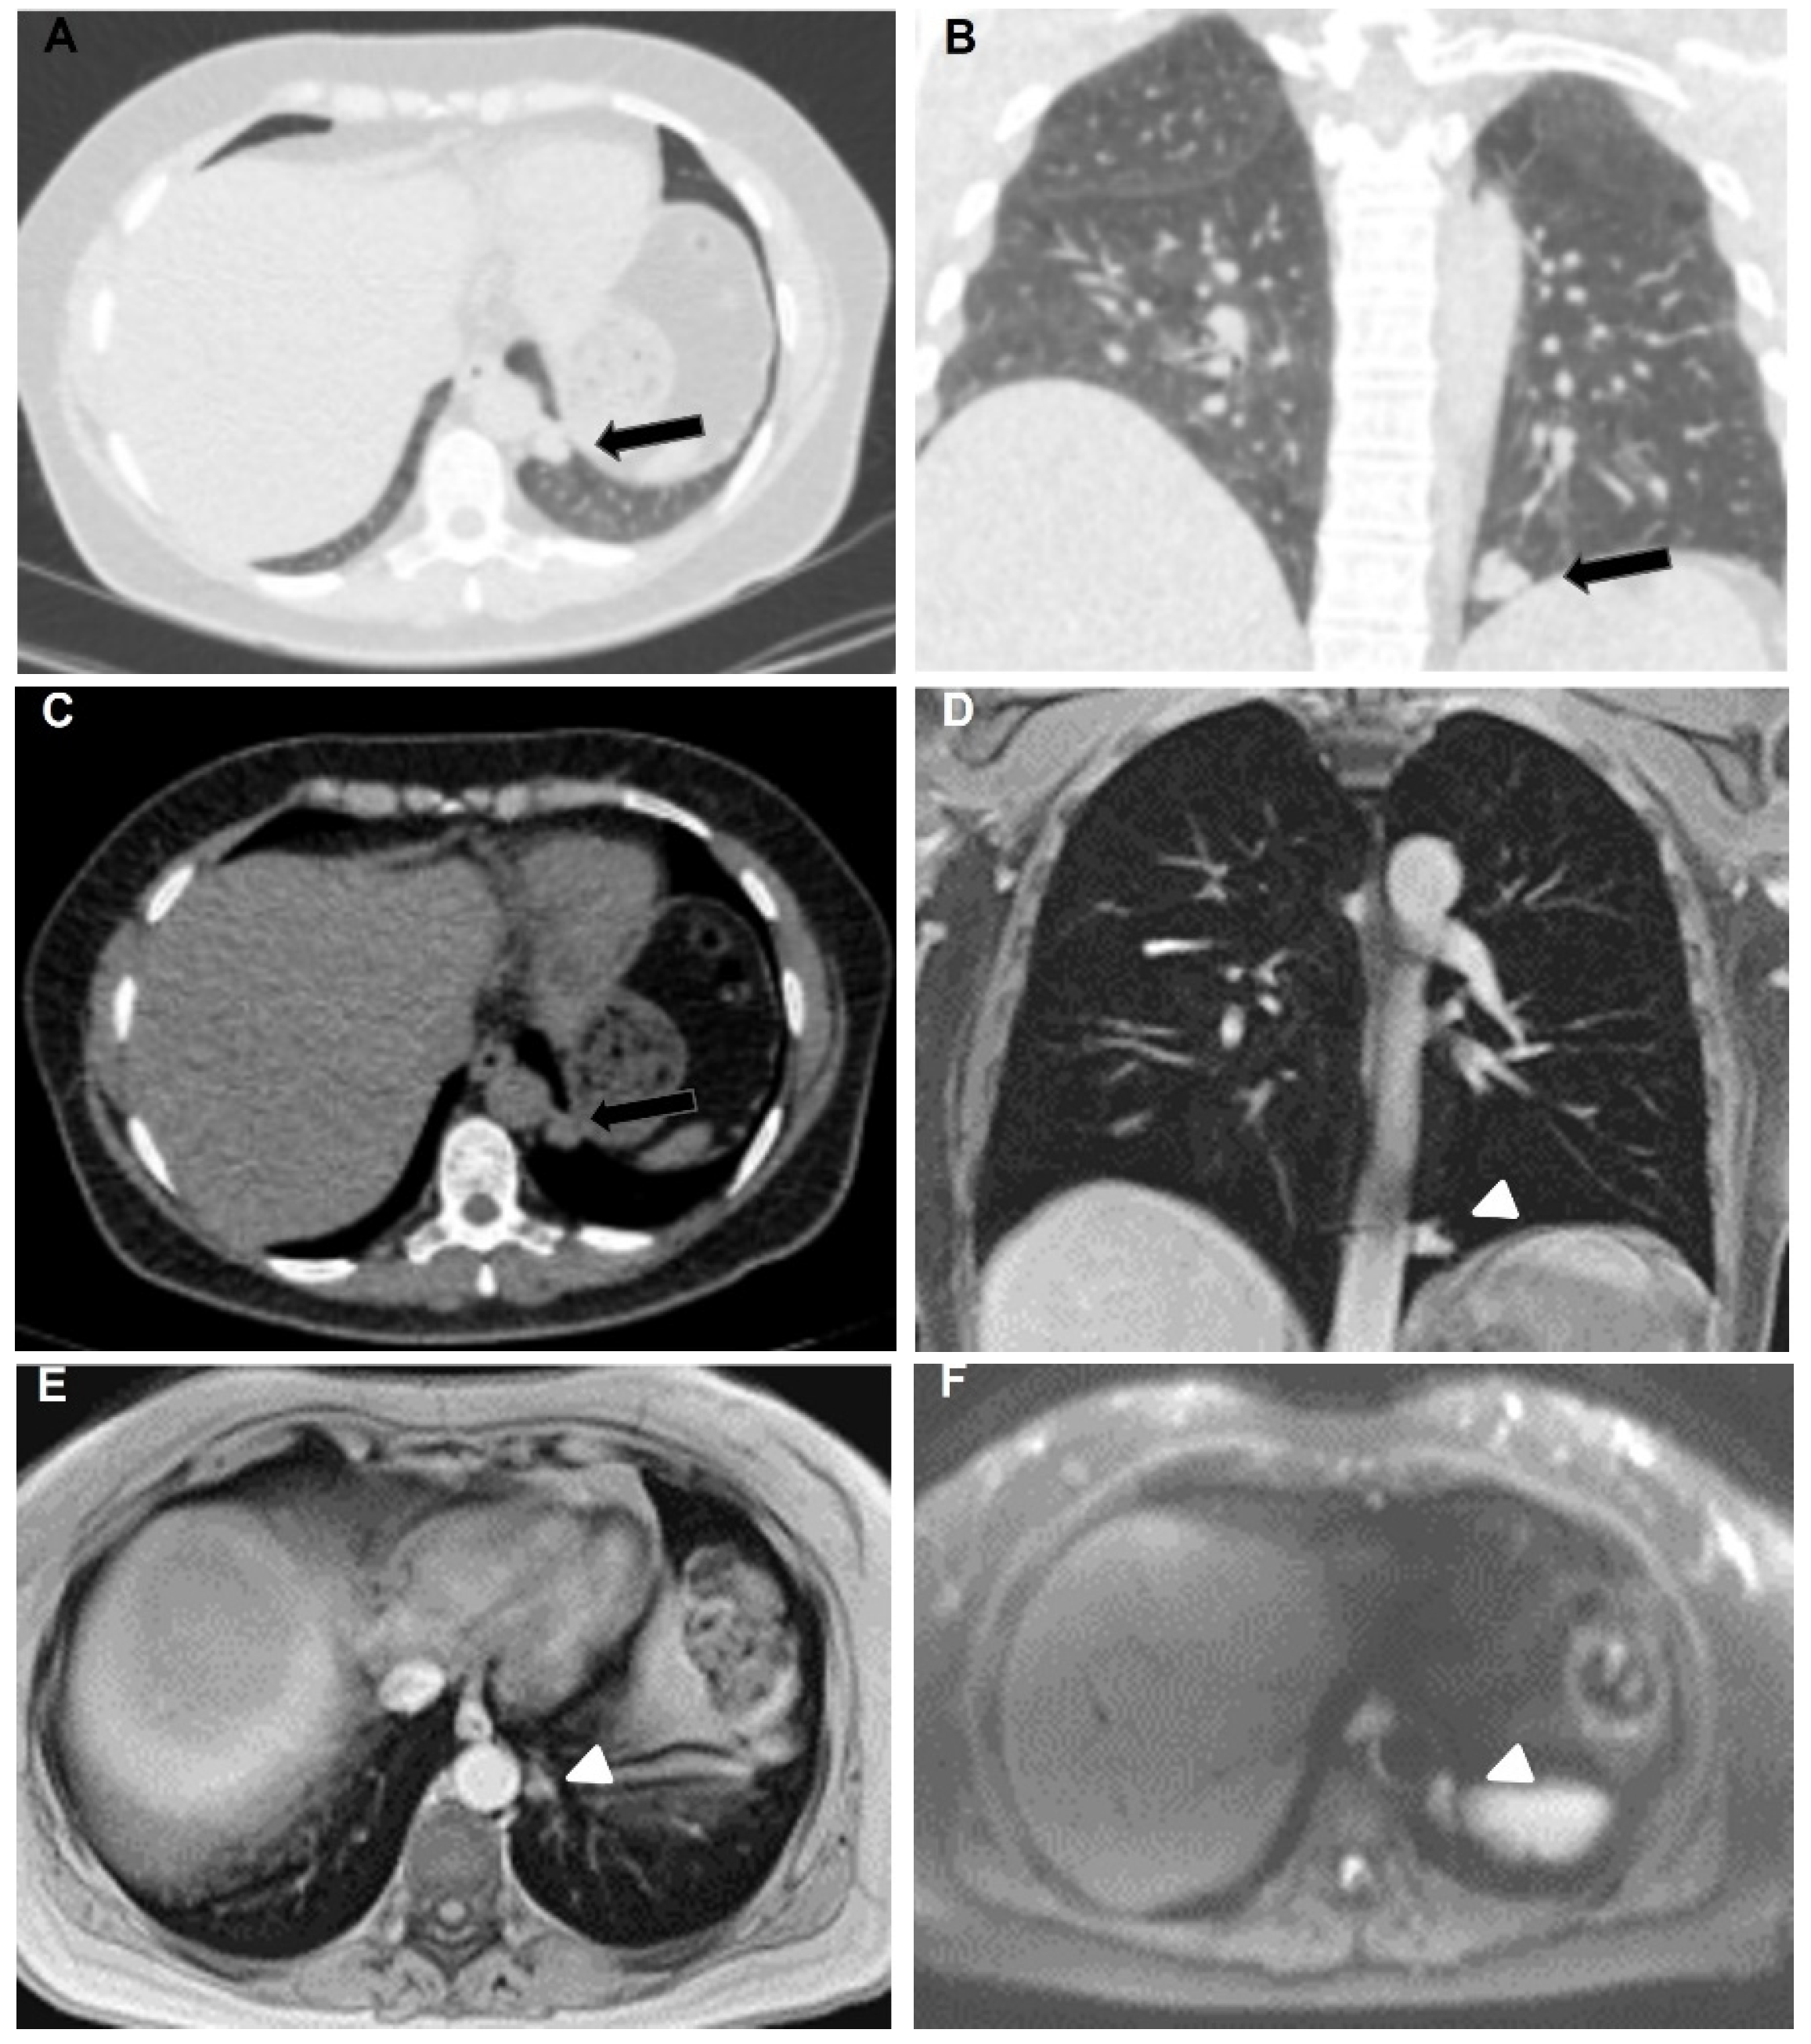

3. Results

3.2. MR Findings

4. Discussion